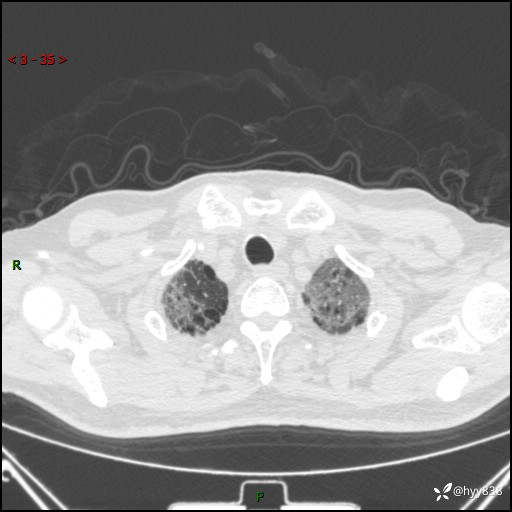

患者性别:男

患者年龄:64岁

简要病史:肝内胆管癌综合治疗后2周余,咳嗽、发热,咳白色泡沫痰。

辅助检查:CT

临床诊断:感染?

讨论:病变性质?